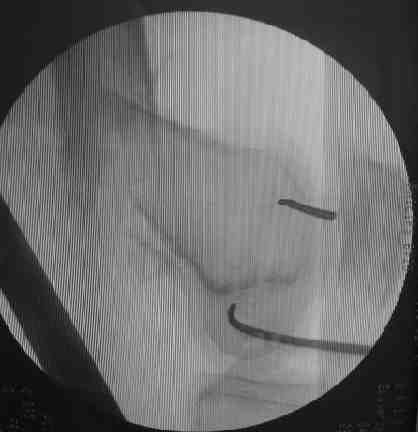

Если перелом диафизарный, в периферическом отломке достаточно одной спицы в переднем отделе мыщелков. Если более дистальный - вводим 2 спицы, ближе к фокусам кондилярного "эллипса". Так они не мешают ни анте-, ни ретроградному введению (см. картинку)

.

Мы практически всегда делаем ретроградный остеосинтез бедра через разрез 1,5 см. До разреза вводим спицу в intercondylar notch по направлению канала. Убедившись по обеим проекциям, что она находится там, где надо, делаем прокол и используем канюлированное шило 13 мм.